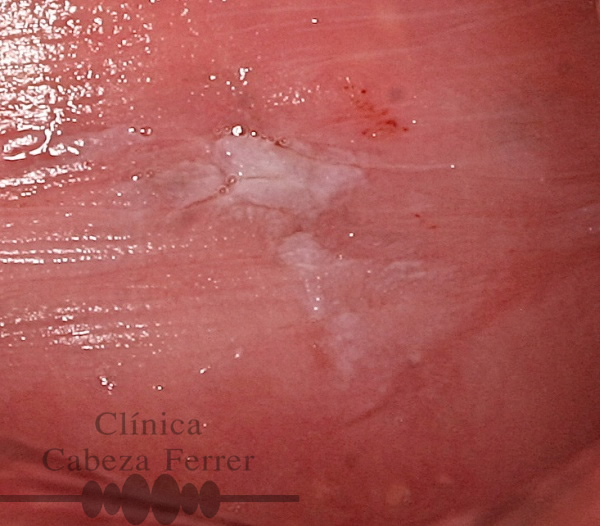

Las manchas blancas de la boca exigen un control odontológico riguroso y frecuente. El alcohol y el tabaco son factores irritativos locales.

- Si tiene una úlcera o mancha en la mucosa de la boca, en la lengua o en el labio que lleva más de 15 días sin cicatrizar.

Como es lógico el diagnóstico precoz es el mejor tratamiento de los tumores bucales. En La Clínica Cabeza Ferrer realizamos exploraciones para detectar el cáncer oral. Es un proceso sencillo, rápido, no invasivo e indoloro. Una vez que el examen ha terminado, si hay evidencia de lesiones u otros signos, se realiza una biopsia.